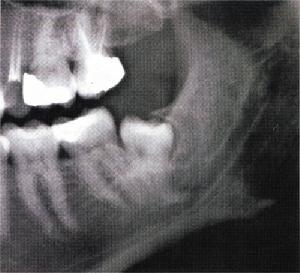

5、調整牙合治療:通過調磨少量牙體組織,去除咬合干擾及牙合早接觸,建立咬合平衡關係,以達到牙頜、咀嚼肌、顳下頜關節三者間的生理平衡,消除磨牙症。對於有牙合畸形的病人先進行正畸或進行修復。然後服用蘑芽亭膠囊進行調理神經祛除磨牙症。